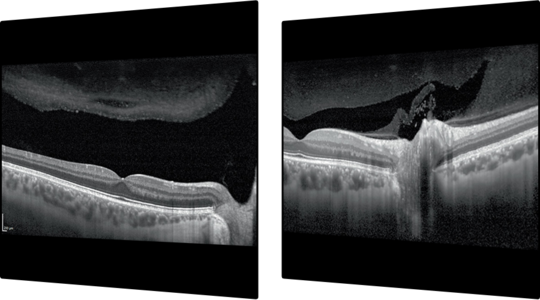

OCT Angiography Module

Non-invaziv vasküler görüntüleme: SPECTRALIS® OCT Angiografi Modülü, 5.7 μm / piksel çözünürlük ile yüksek kaliteli OCTA görüntüleri sunar. TruTrack Aktif Göz Takibi’nin hassasiyeti ile birleştirildiğinde, OCTA Modülü ince kapiller ağların detaylı şekilde görüntülenmesini sağlar. 3.9 μm / piksel eksen çözünürlüğü, dört histolojik olarak doğrulanmış retinal vasküler pleksusun segmentasyonuna izin verir. Yüzeysel ve derin vasküler pleksuslar içindeki özel tabakaların ayrı ayrı görüntülenmesine olanak sağlar. Projeksiyon artefaktı giderme (PAR) aracı, OCTA görüntülerinden artefaktları kaldırmak için yüzeysel vasküler pleksustan bilgi sağlar. Bu, vasküler yapı ve patolojinin daha hassas şekilde görüntülenmesine olanak tanır.